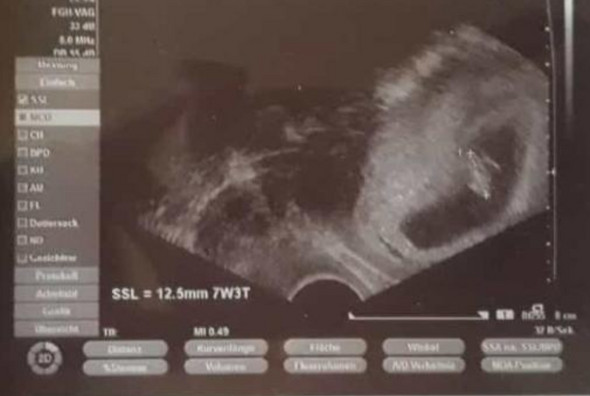

10 SSW - Riskante Zeit vorbei. Ich persönlich habe hier von sehr vielen gelesen die in der 10. 10 SSW - Riskante Zeit vorbei. Viele Grüße und nochmal besten Dank für Ihre Einschätzung. SSW langsam zurück und das Stadium der kritischen Frühschwangerschaft bis zur 12. Das Risiko einer Fehlgeburt sinkt ab jetzt ganz rapide. Was passiert bei einer Fehlgeburt. Das Risiko dass eine Schwangerschaft in einer Fehlgeburt vor der 20. SSW ist für viele werdende Eltern eine magische Grenze die nicht selten großes Aufatmen hervorruft.

Sind die ersten zwölf Wochen der Schwangerschaft geschafft fällt die Wahrscheinlichkeit einer Fehlgeburt demnach geringer aus. Andererseits ist auch nach der 12. Schwangerschaftswoche SSW spürst dann ist das auch völlig normal du zählst eben einfach zu den glücklichen Schwangeren die weniger oder kaum Schmerzen während ihrer Schwangerschaft haben. Woche ja die Fetalphase beginnt in der das FG-Risiko im Vergleich zur Embryonalphase niedriger ist. SSW ist das Fehlgeburtsrisiko so in etwa bei 12 und nach der vollendeten 12. Wenn du bisher trotz erwiesener Schwangerschaft keine Anzeichen mehr in der 10. 10 SSW - Riskante Zeit vorbei.